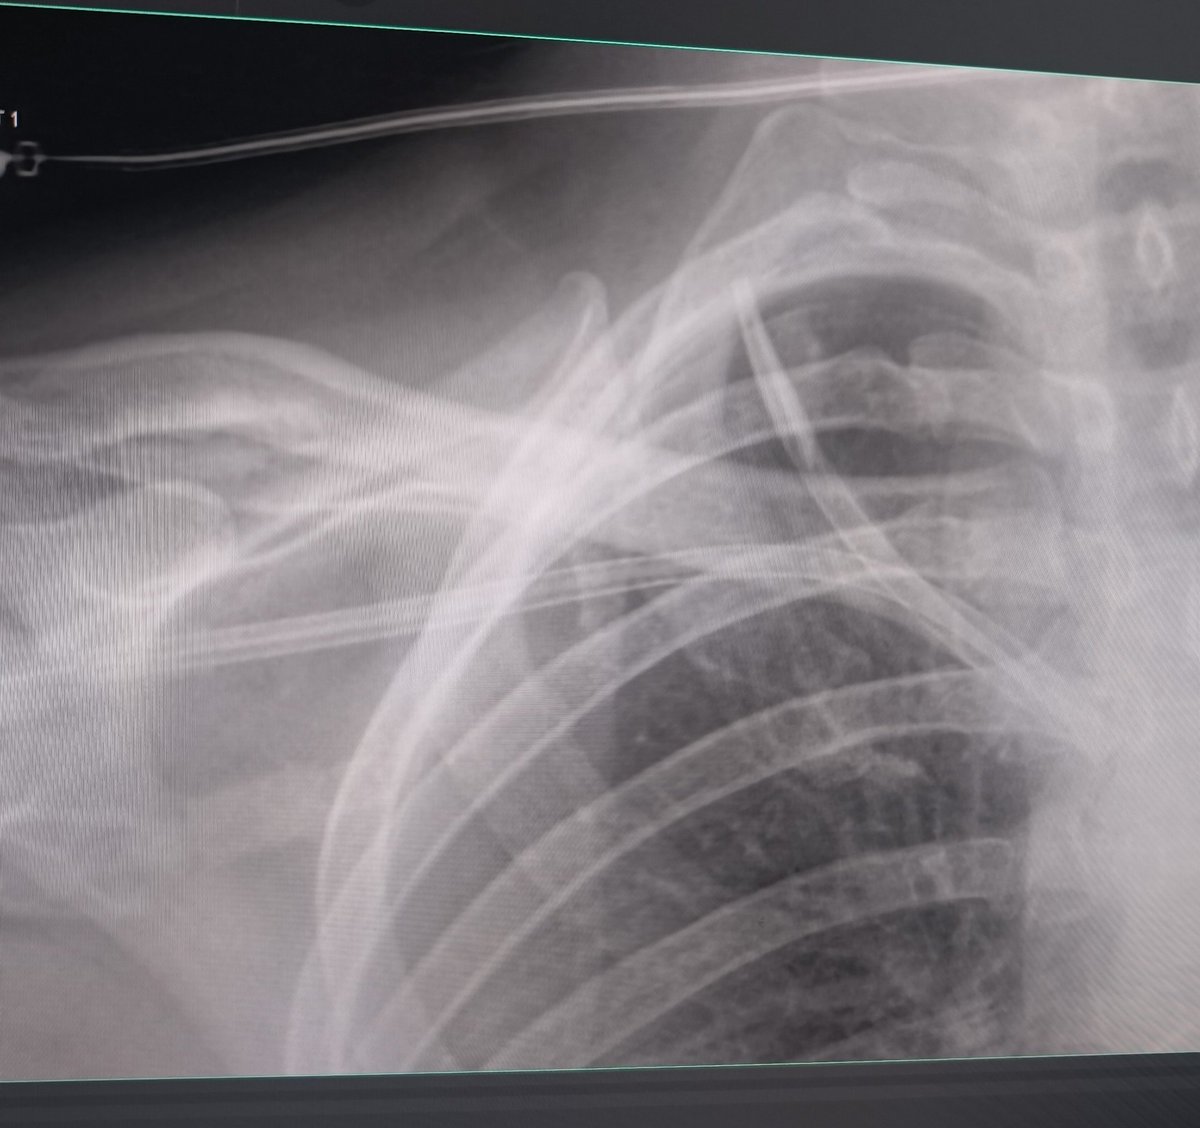

Cuando pones un catéter para hemodiálisis tienes 3 oportunidades (una guía, dos dilatadores y un catéter) que te dará la vida para rectificar tu decisión de meter todo a la puta fuerza. 🤬